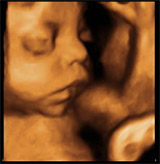

En la semana 32 de embarazo gemelar monocorial (una sola placenta) te realizarán una ecografía para comprobar el latido cardiaco de cada bebé. En ese mismo estudio de ultrasonidos el médico va a valorar el crecimiento de cada uno de los bebés mediante la medición de la cabeza (diámetro biparietal), el abdomen (circunferencia abdominal) y la longitud del fémur.

Esta prueba se acompañará de una ecografía Doppler de arterias umbilicales de cada feto. De esta forma se puede saber si están recibiendo el oxígeno y los nutrientes necesarios para desarrollarse sin carencias.

La ecografía en el tercer trimestre de embarazo gemelar no difiere de la que se realiza en las gestaciones únicas. Sobre todo se valora el crecimiento de ambos fetos para descartar el crecimiento intrauterino retardado de uno de los fetos o de ambos.

Quizás lo más importante de esta ecografía es valorar si los dos fetos están creciendo adecuadamente y descartar posibles discordancias de crecimiento o un cuadro llamado crecimiento intrauterino restringido de uno de los dos fetos. Es importante también valorar cómo están colocadas las placentas, ya que esta ecografía nos permite detectar algunas complicaciones que son más frecuentes en las gestaciones gemelares como la placenta previa o la vasa previa. También se puede ver la inserción de los dos cordones umbilicales en ambas placentas. La cantidad de líquido amniótico en ambas bolsas es una medida que no debe faltar en la ecografía, pues es un indicador de bienestar fetal.